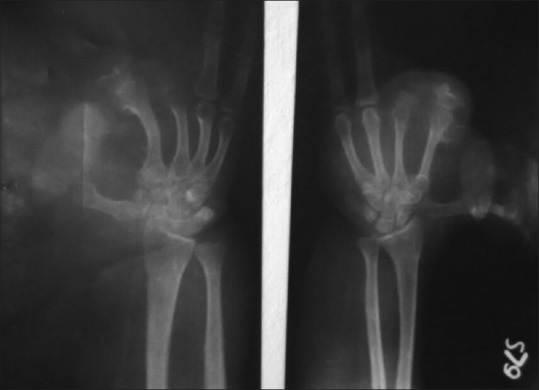

A 3-year-old female child presented with a progressive disproportionate enlargement of the second and third toes of the right foot since birth [Figure 1]. There were no history of any pain or neurovascular symptoms and also no family history of extremity gigantism. The developmental milestones were according to the age. On physical examination, there was nontender enlargement of the second and third toes of the right foot. No overlying cutaneous changes, pitting edema, or bruit was seen. All the other extremities were found to be normal on examination. A plain X-ray of the right foot was performed that revealed soft-tissue swelling involving the second and third toes with hypertrophy of the phalanges [Figure 2]. Gray-scale ultrasound and color flow Doppler revealed diffuse soft-tissue thickening, without any abnormal calcifications or abnormal blood flow. Fine-needle aspiration from the second digit yielded blood-tinged fatty aspirate. Smears examined revealed fragments of mature adipose tissue [Figure 3]. No malignant cells were identified. The background revealed fat droplets admixed with red blood cells (RBCs) and few inflammatory cells. Correlating the lesion's clinical presentation, imaging and cytological finding possibility of benign mesenchymal lesion of lipomatous origin was considered with a differential diagnosis of ML and fibrolipomatous hamartoma. Debulking surgery was performed. Histopathological examination of the sent material showed mature fibroadipose tissue involving the subcutaneous plane. The nerve sheath and the surrounding muscle fibers were free of fatty infiltration. Thus, a definitive diagnosis of ML was rendered which confirmed the initial cytological possibilities.

| Figure 2:X-ray image showing hypertrophy of soft tissues of the 2nd and 3rd digit of the right foot